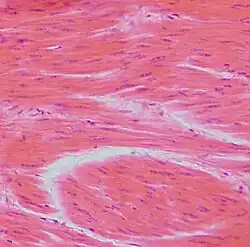

Dense Regular Connective Tissue

Parallel fibers of collagen. This connective tissue makes up ligaments and tendons